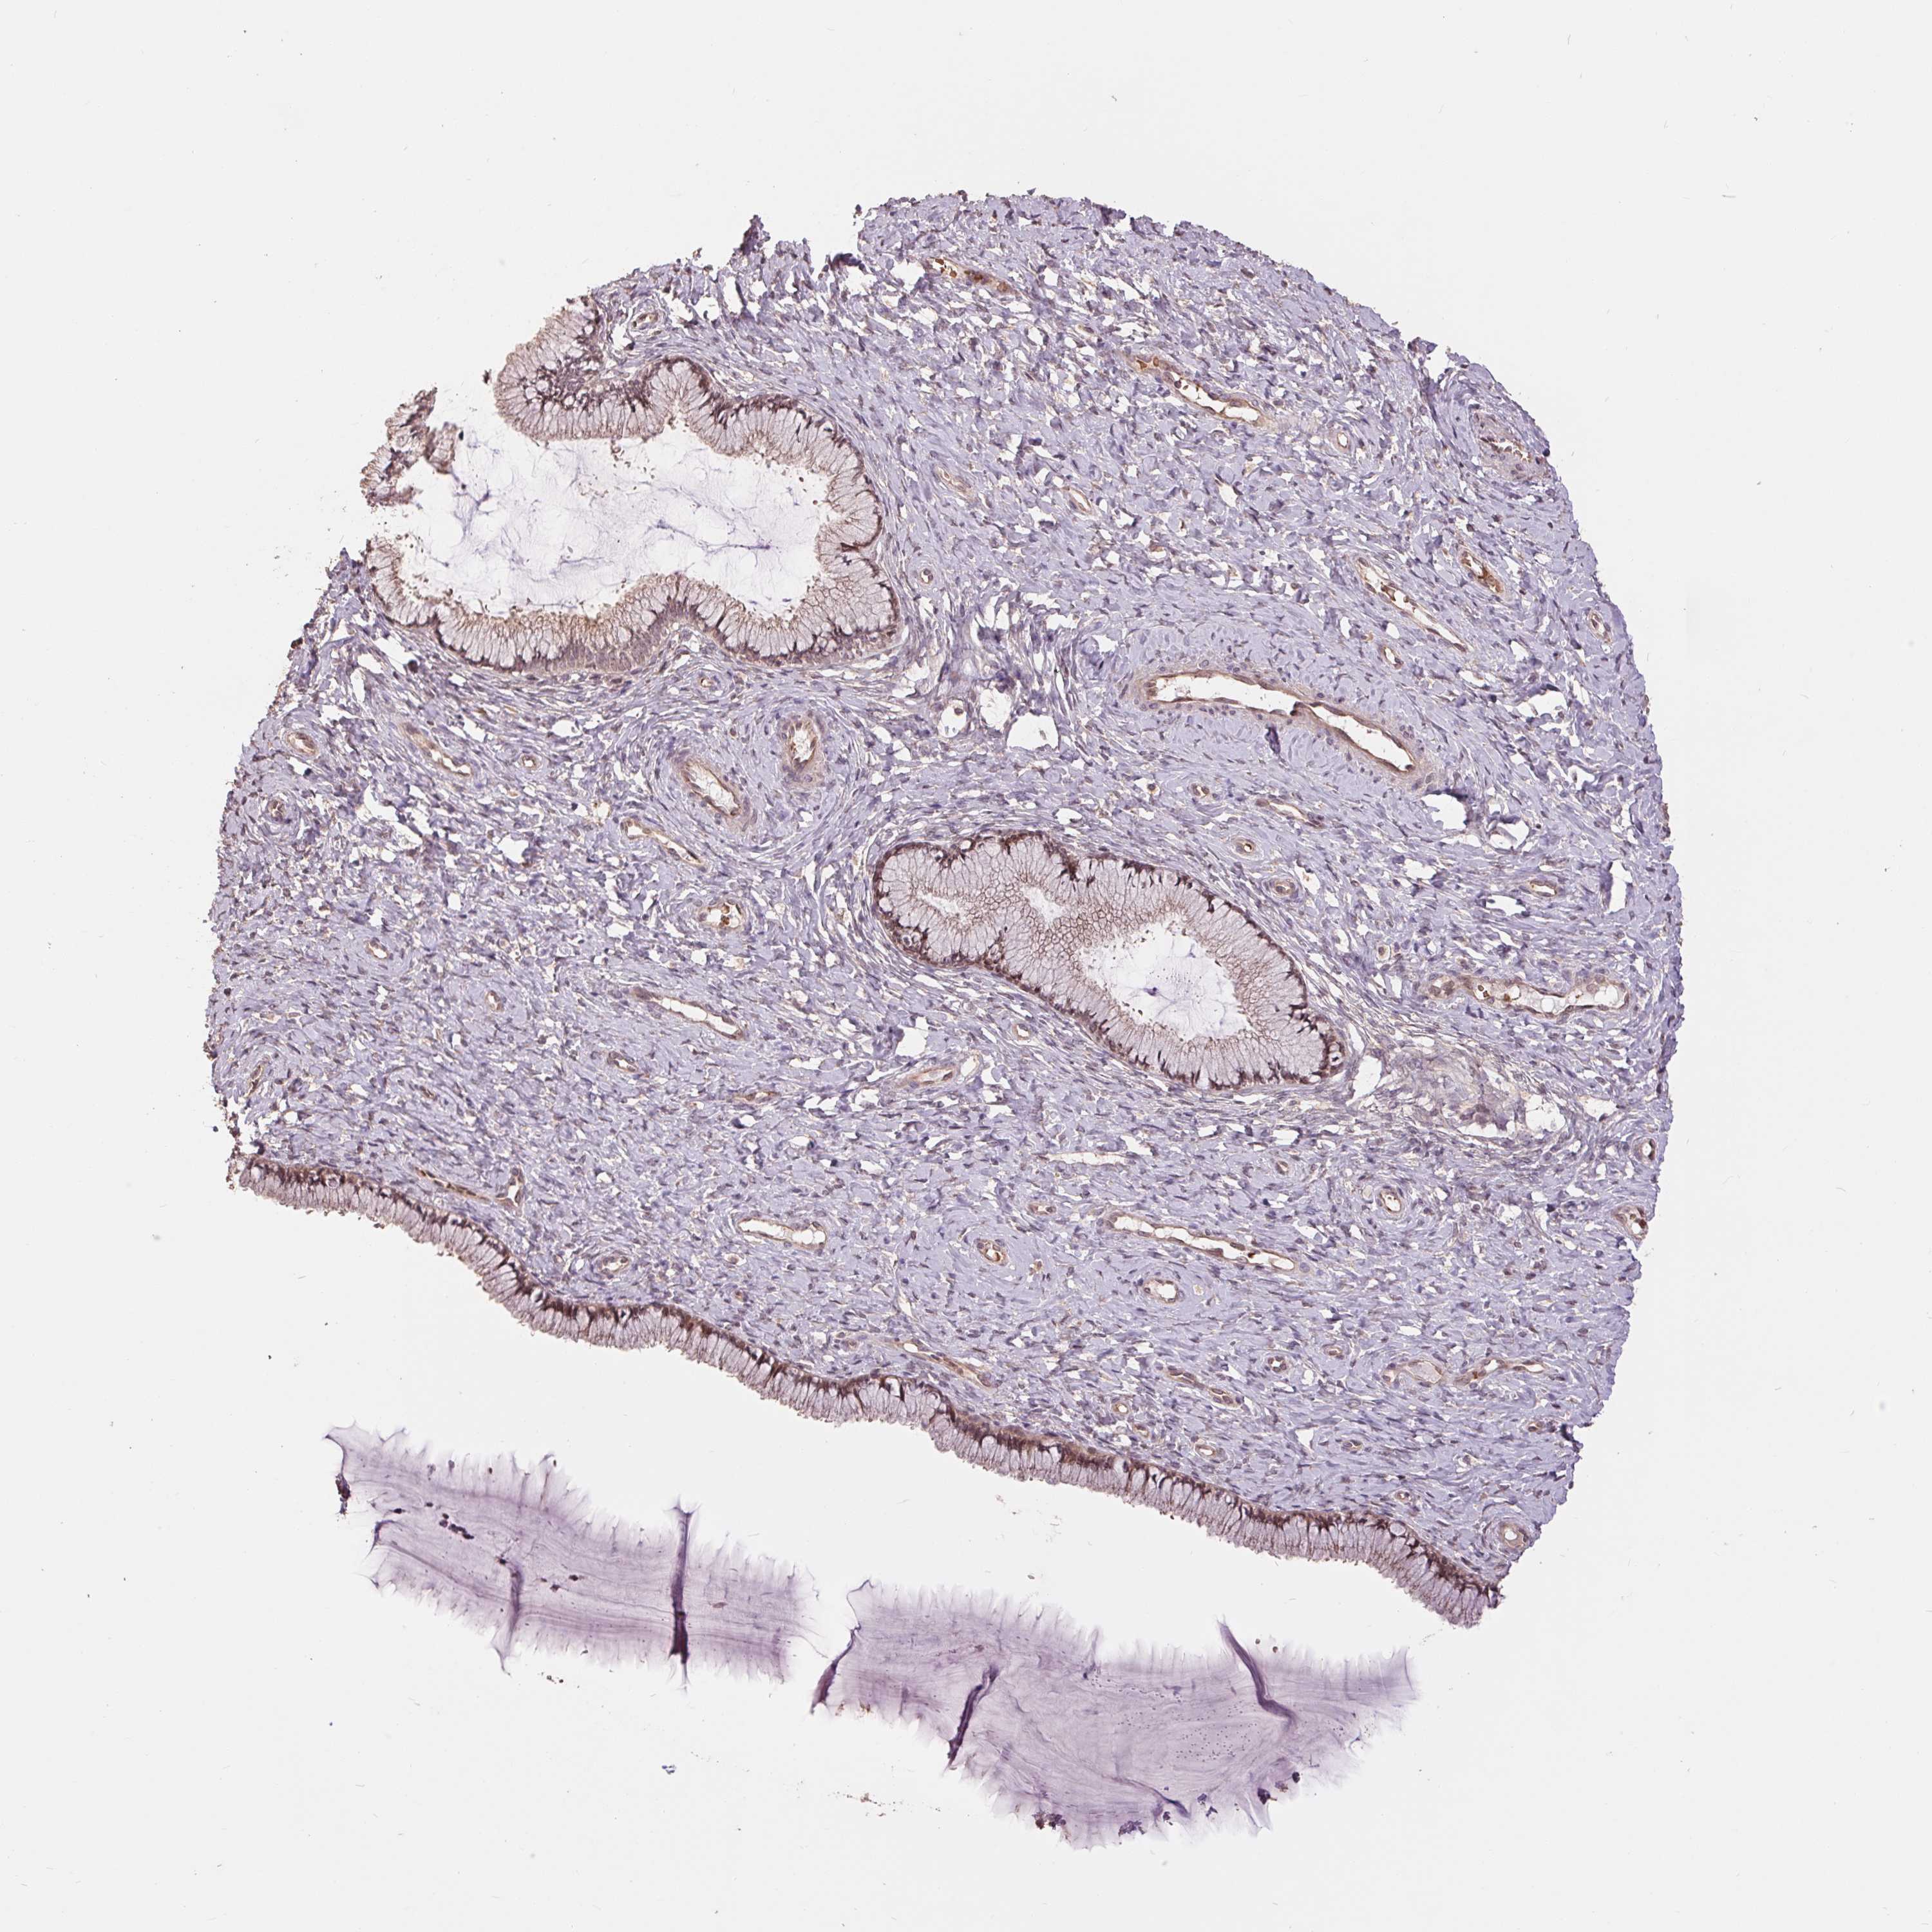

Antibody staining in the annotated cell types in the current human tissue is reported as not detected, low, medium, or high. This score is based on the staining intensity and fraction of stained cells.